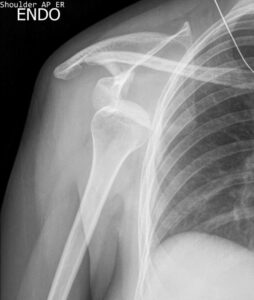

- Visible deformity in the shoulder

The severity of shoulder dislocation symptoms depends on how completely the bones are separated. Patients with partial dislocation or subluxation will experience pain, but they may still have limited use of their arm. Patients with a complete dislocation, meanwhile, may fully lose the ability to move their arm.